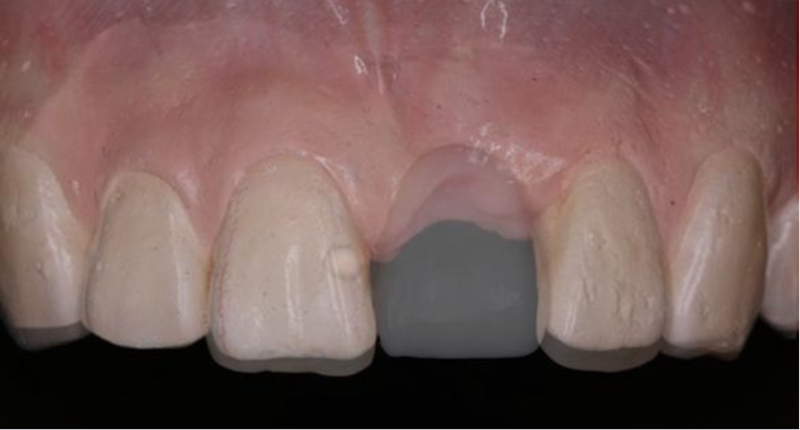

戴入患者口內(nèi),檢查U型管就位與石膏模型就位一致

檢查U型管及印模在口內(nèi)就位與石膏模型上一致

患者佩戴此U型管開合拍攝CBCT,其中可以獲得缺牙區(qū)修復(fù)體的切端及齦緣等信息

患者佩戴此U型管開合拍攝CBCT,U型管中的放射標記點清晰顯影